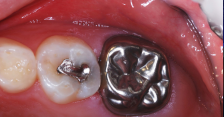

A 9-year-old presented with hypoplasia, hypocalcification, and caries.

Figure 1

A 9-year-old boy had a partially erupted mandibular first molar with much hypocalcification of the occlusal surface and a large caries lesion involving the occlusal and buccal surfaces (Figure 1). The patient complained of continuing sensitivity to cold stimulus and air inspiration. Because the tooth was only partially erupted, consideration for stainless steel crown full coverage had to be delayed. As an interim repair, it was decided to debride the carious tooth substance and place a light-hardened calcium silicate/mineral trioxide aggregate (MTA) liner, followed by a bonded restoration. After inferior alveolar block anesthetic injection and cotton roll isolation, cavity outline form was cut using a high-speed, water-cooled, medium-grit cylindrical diamond bur (Figure 2). Insufficient eruption precluded use of a rubber dam. A large, round bur at slow speed was used to debride the carious enamel and dentin. The prepared surfaces were swabbed for two 60-second applications of a 5% glutaraldehyde/HEMA solution for desensitization and disinfection of the preparation.6,7 Cavity liner was then injected and spread over the deepest sections of the cavity floor and hardened with the visible light beam (Figure 3). After a self-etching bonding agent was applied over the remaining enamel surfaces, without the need for any type of matrix, an RMGI bioactive ionic resin-based composite was injected, in one portion, into the preparation and spread over the four cusps using a ball burnisher. This restorative complex was then photo-polymerized using two 20-second exposures of the visible light beam (1,200 mW/cm2). The restoration was trimmed and finished with large, round diamond burs at slow speed, and occlusion was evaluated with articulating paper and adjusted.